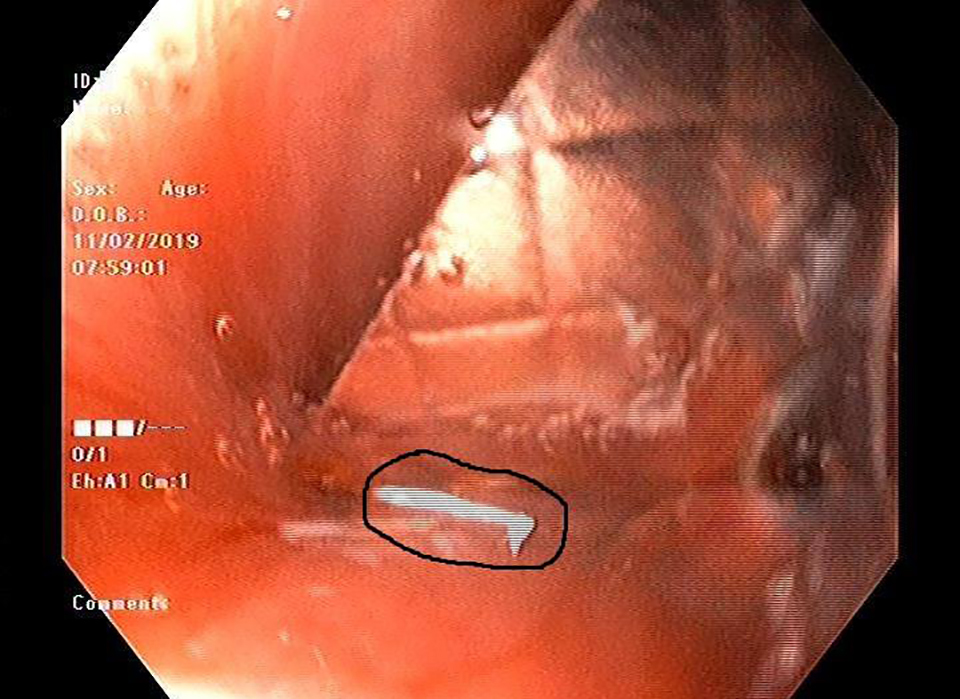

Hình ảnh nội soi cho thấy vỉ thuốc cắm vào thành thực quản bệnh nhân

Trưa ngày 11/2, thông tin từ Bệnh viện Đa khoa tỉnh Hà Tĩnh cho biết, các bác sĩ Khoa Chẩn đoán hình ảnh bệnh viện này vừa nội soi gắp viên thuốc còn nguyên vỉ sắc nhọn trong thực quản cho bệnh nhân N. C. L (65 tuổi), trú tại Phường Trấn Phú, TP Hà Tĩnh.

Sau khi hội chẩn, các bác sĩ ở Khoa Chẩn đoán hình ảnh đã gắp ra 1 vỉ thuốc còn nguyên vỏ với các cạnh sắc nhọn, cắm vào thành thực quản, đường kính khoảng 2 x 2,5cm.